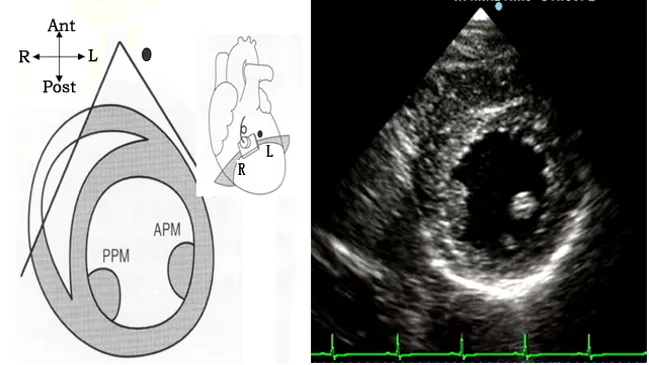

胸骨旁乳头肌水平短轴切面

● 探头位置:探头置于胸骨左缘3、4肋间,声速恰好横切两组乳头肌。

● 观察内容

腔室大小:左室。

室壁厚度:中间部整个左室壁。

室壁活动:中间部整个左室壁。